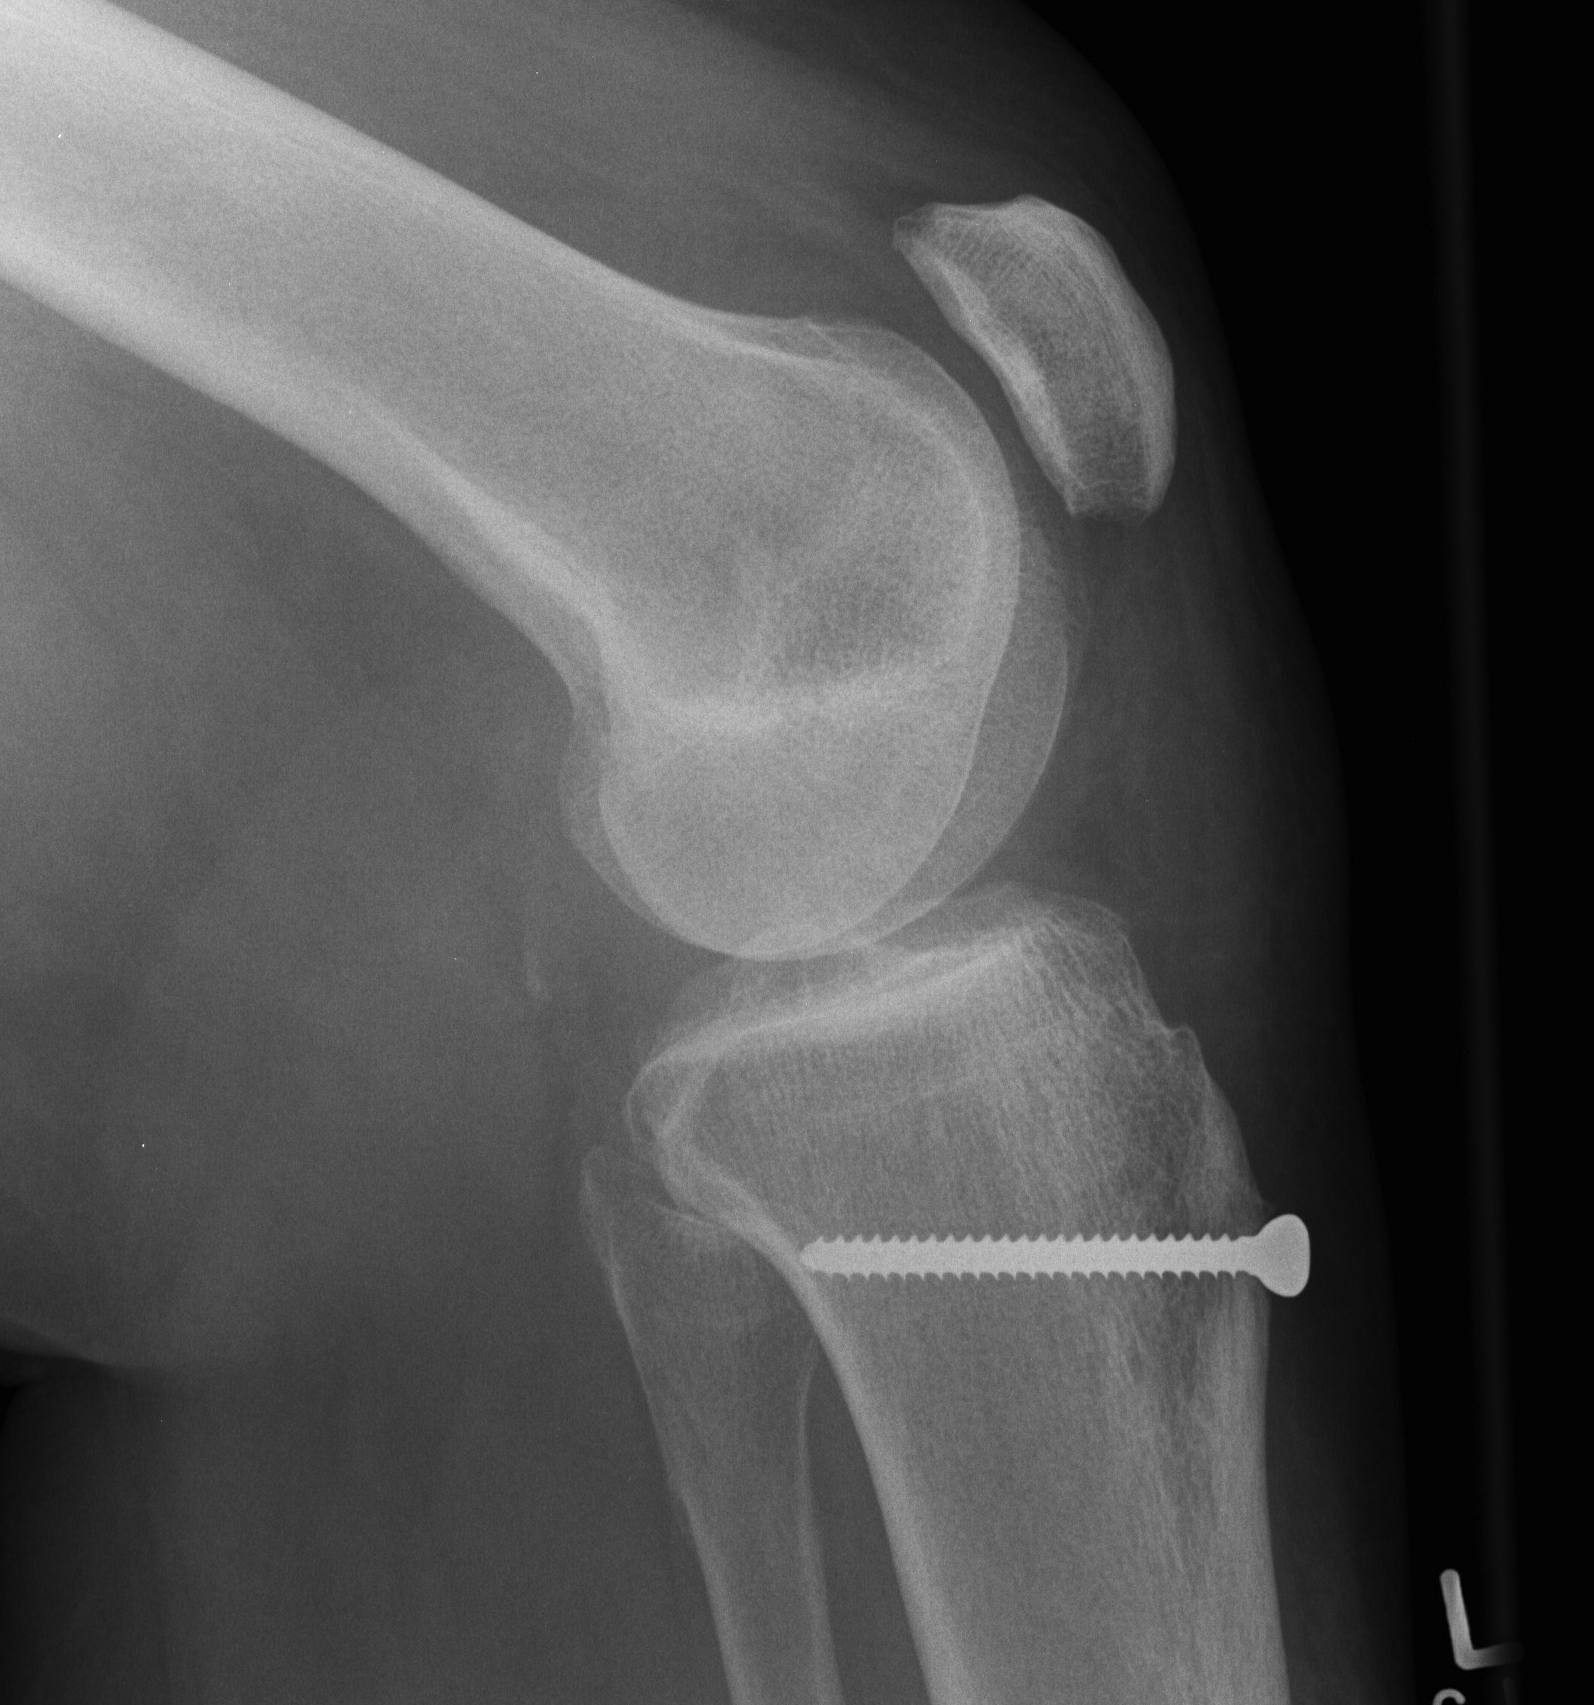

- osteotomy 1.5 cm deep, 6 cm long

- angle osteotomy 45 degrees / use k wires to guide

- fix with two screws

- secure with singe 4.5 mm bi-cortical lag screw